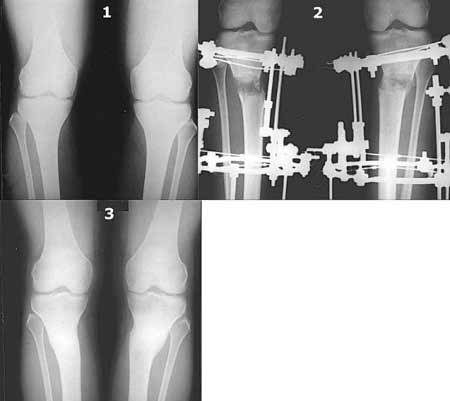

Картинки - в приложении.Будут вопросы - готов ответить.

Вот ещё картинки, которые отправлял в Ортопод. Коррекция кривизны и удлинение на 3 см.